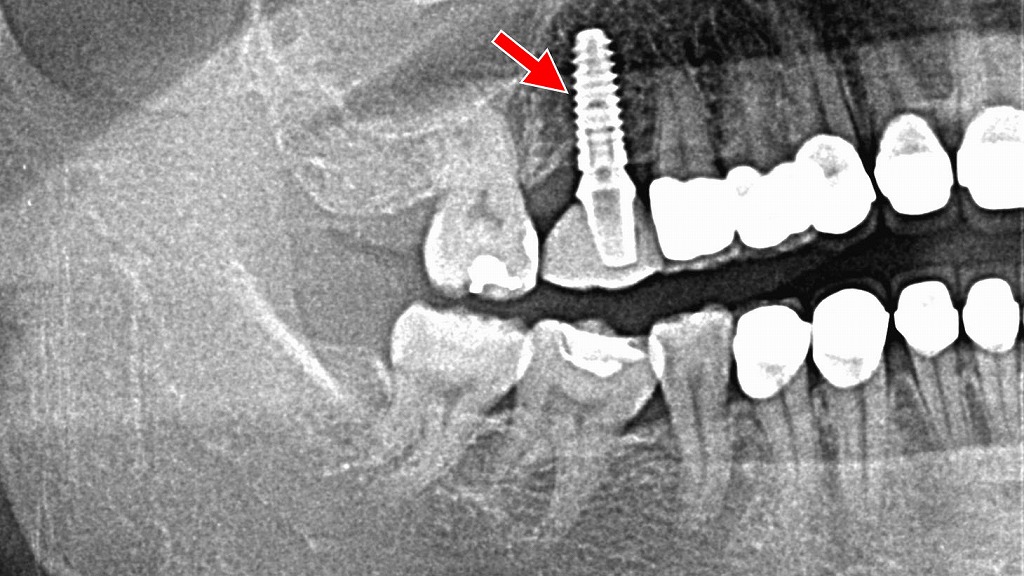

🔍 左右の下あごに乳歯が残存 第二小臼歯の先天欠損症例

このパノラマレントゲンでは 左右の下顎に第二乳臼歯が残存 しており、本来生えてくるはずの 第二小臼歯(永久歯)が先天的に欠損 している状態が確認できます。

① 両側の下顎:第二乳臼歯の残存(矢印付近)

- 赤い矢印で示されている位置に 乳歯(第二乳臼歯)が残ったまま になっています。

- 通常、第二乳臼歯は12歳前後で抜け、下から第二小臼歯が生えてきます。

- 本症例では、その 永久歯の芽(歯胚)が存在せず、乳歯が自然脱落しない状態 です。

- 乳歯の根はやや短く、加齢とともに吸収していく可能性がありますが、現在は保持されています。

② 第二小臼歯の先天欠損

- 下顎の左右とも、第二小臼歯の歯胚がレントゲン上に確認できません。

- 先天欠損は比較的よく見られる歯の発育異常で、第二小臼歯はその代表的な部位です。

- 永久歯が無いことで、乳歯が長期的に機能しているケースもあります。

③ 咬合や将来への影響

- 乳歯は永久歯よりも寿命が短く、将来的に

- すり減り

- 破折(割れ)

- 歯根吸収による動揺

が起こる可能性があります。

- その際は、

- インプラント

- ブリッジ

- 矯正治療を含めたスペースクローズ

などが選択肢になります。

インプラント

上顎6番欠損に対するインプラント治療の術前・術中・術後の経過です。

欠損部の状態を正確に診断したうえで、骨の質や量を考慮しながらインプラントを適切な位置に埋入しました。

術後の被せ物を装着したレントゲンでは、インプラントが骨内に安定して固定されていることが確認でき、噛む機能と咬合の回復を図っていきます。